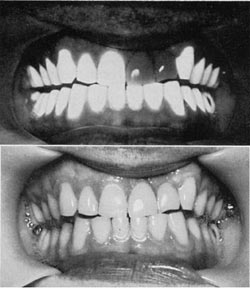

Tredinnick was the first to describe the colour recording of ultraviolet fluorescence photography in1955, in a paper in Medical and Biological Illustration. In this the author showed examples of colour fluorescence photography of the teeth, bacterial plates, specimens and how industrial oil on the back of a hand fluoresced. His examples of bacterial plates showed H. Pertussis having strong characteristic blue/white fluorescence. Also in this paper he showed how a tumour in a bladder specimen was clearly delineated because it did not fluoresce as strongly as the background tissue. He demonstrated that the technique could differentiate between false and natural teeth - the false teeth did not fluoresce (Figure 25). He used Phillips mercury vapour lamps in conjunction with Chance OX1 and Wratten 2B filters. Exposures varied from three seconds to three minutes with an aperture of f/6.8 and Ilford D colour film.

Ultraviolet fluorescence of teeth

Figure 25 (left). False teeth do not fluoresce when using the ultraviolet fluorescence technique.